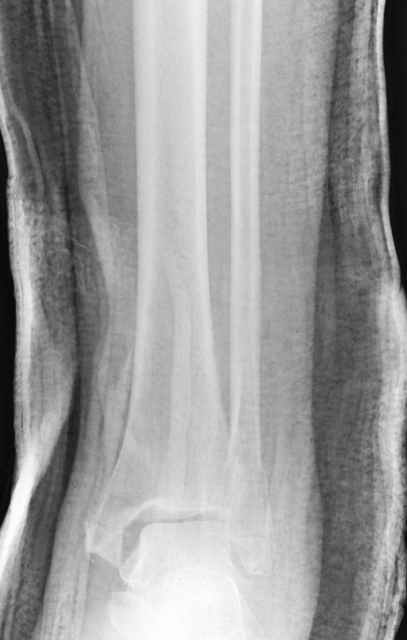

Еще, кстати, о фиксации лодыжки, если уж непременно хочется ее отдельно стабилизировать - при таком характере перелома замечательно должен сработать предложенный проф. Лазаревым с соратниками способ фиксации напряженной V-образной спицей. Опять же, открытая репозиция не нужна, мы делаем непрямую репозицию именно аппаратом. В приложении пример, там перелом малоберцовой куда менее поперечный, чем в данном случае, но все равно получилось закрыто без пластинки.

A propos fibular fixation if one is eager to stabilize it separately. In the fracture pattern a way of closed fixation by V-shaped stressed wire (advanced by colleagues from Moscow, prof. Lazarev A.F. et al.) must be excellent. We use indirect closed reduction by the external fixator. Example attached, that fibular fracture is even more suitable for plating but the wire did the job.